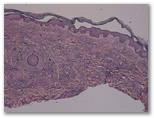

1532- Paciente con artralgias, paraproteinemia IgA y lesiones cutáneas

progresivas de varios meses de evolución que se ilustran en las imágenes

2. Eritema elevatum diutinum